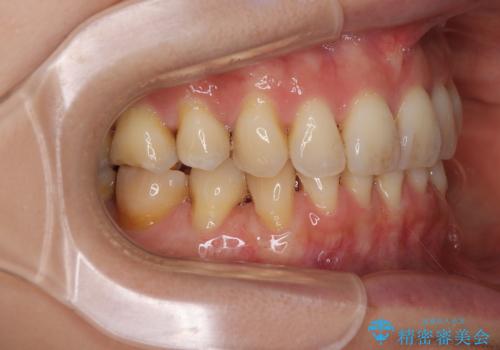

移植片には、極力角化歯肉が多く残るようにし、被覆するだけでなく、歯肉の厚みを増やし、角化歯肉を回復させることができました。